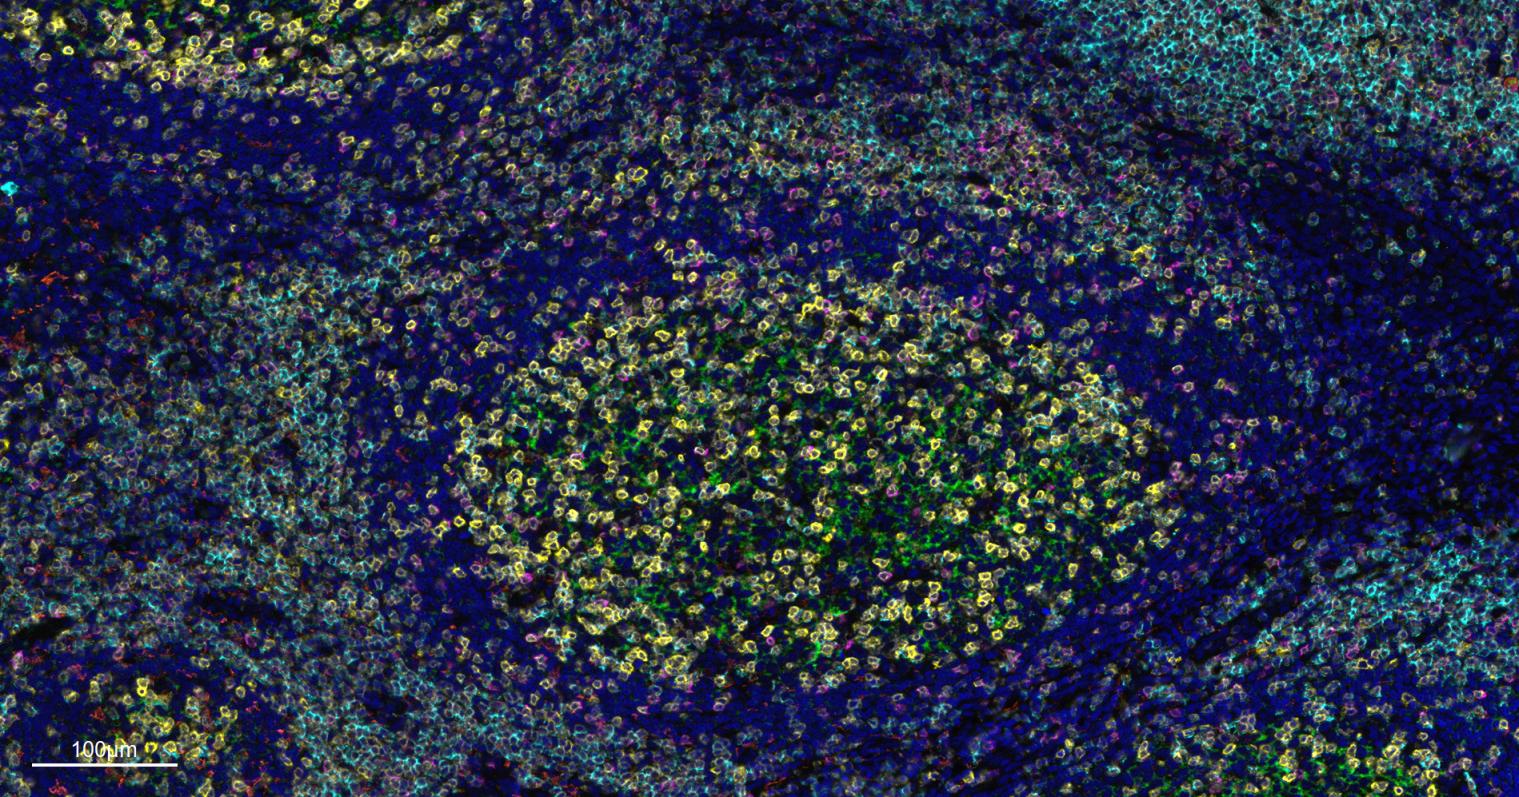

Paraformaldehyde-fixed, paraffin embedded Human Tonsil. Merged staining of anti-CD8A (bsm-34251M; 1:200; pink) anti-CD4 (bsm-52469R; 1:200; light blue) anti-CD3E (bsm-60002R; 1:200; green) anti-CD68 (bsm-60634R; 1:200; white) anti-CD11c (bsm-61135R; 1:200; orange) and anti-CD20 (bsm-63327R; 1:200; yellow) DAPI (dark blue) was used as a nuclear counter stain.

Paraformaldehyde-fixed, paraffin embedded Human Tonsil. Merged staining of anti-CD68 (bsm-60634R; 1:200; red) anti- CD20 (bsm-63327R; 1:200; white) anti-CD3E (bsm-60002R; 1:200; light blue) anti-CD4 (bsm-52469R; 1:200; rose red) anti-Ki67 (bsm-52455R; 1:200; bean green) anti-Vimentin (bsm-33170M; 1:200; yellow) and anti-Pan Cytokeratin (bsm-34137M; 1:150; green) DAPI (dark blue) was used as a nuclear counter stain.